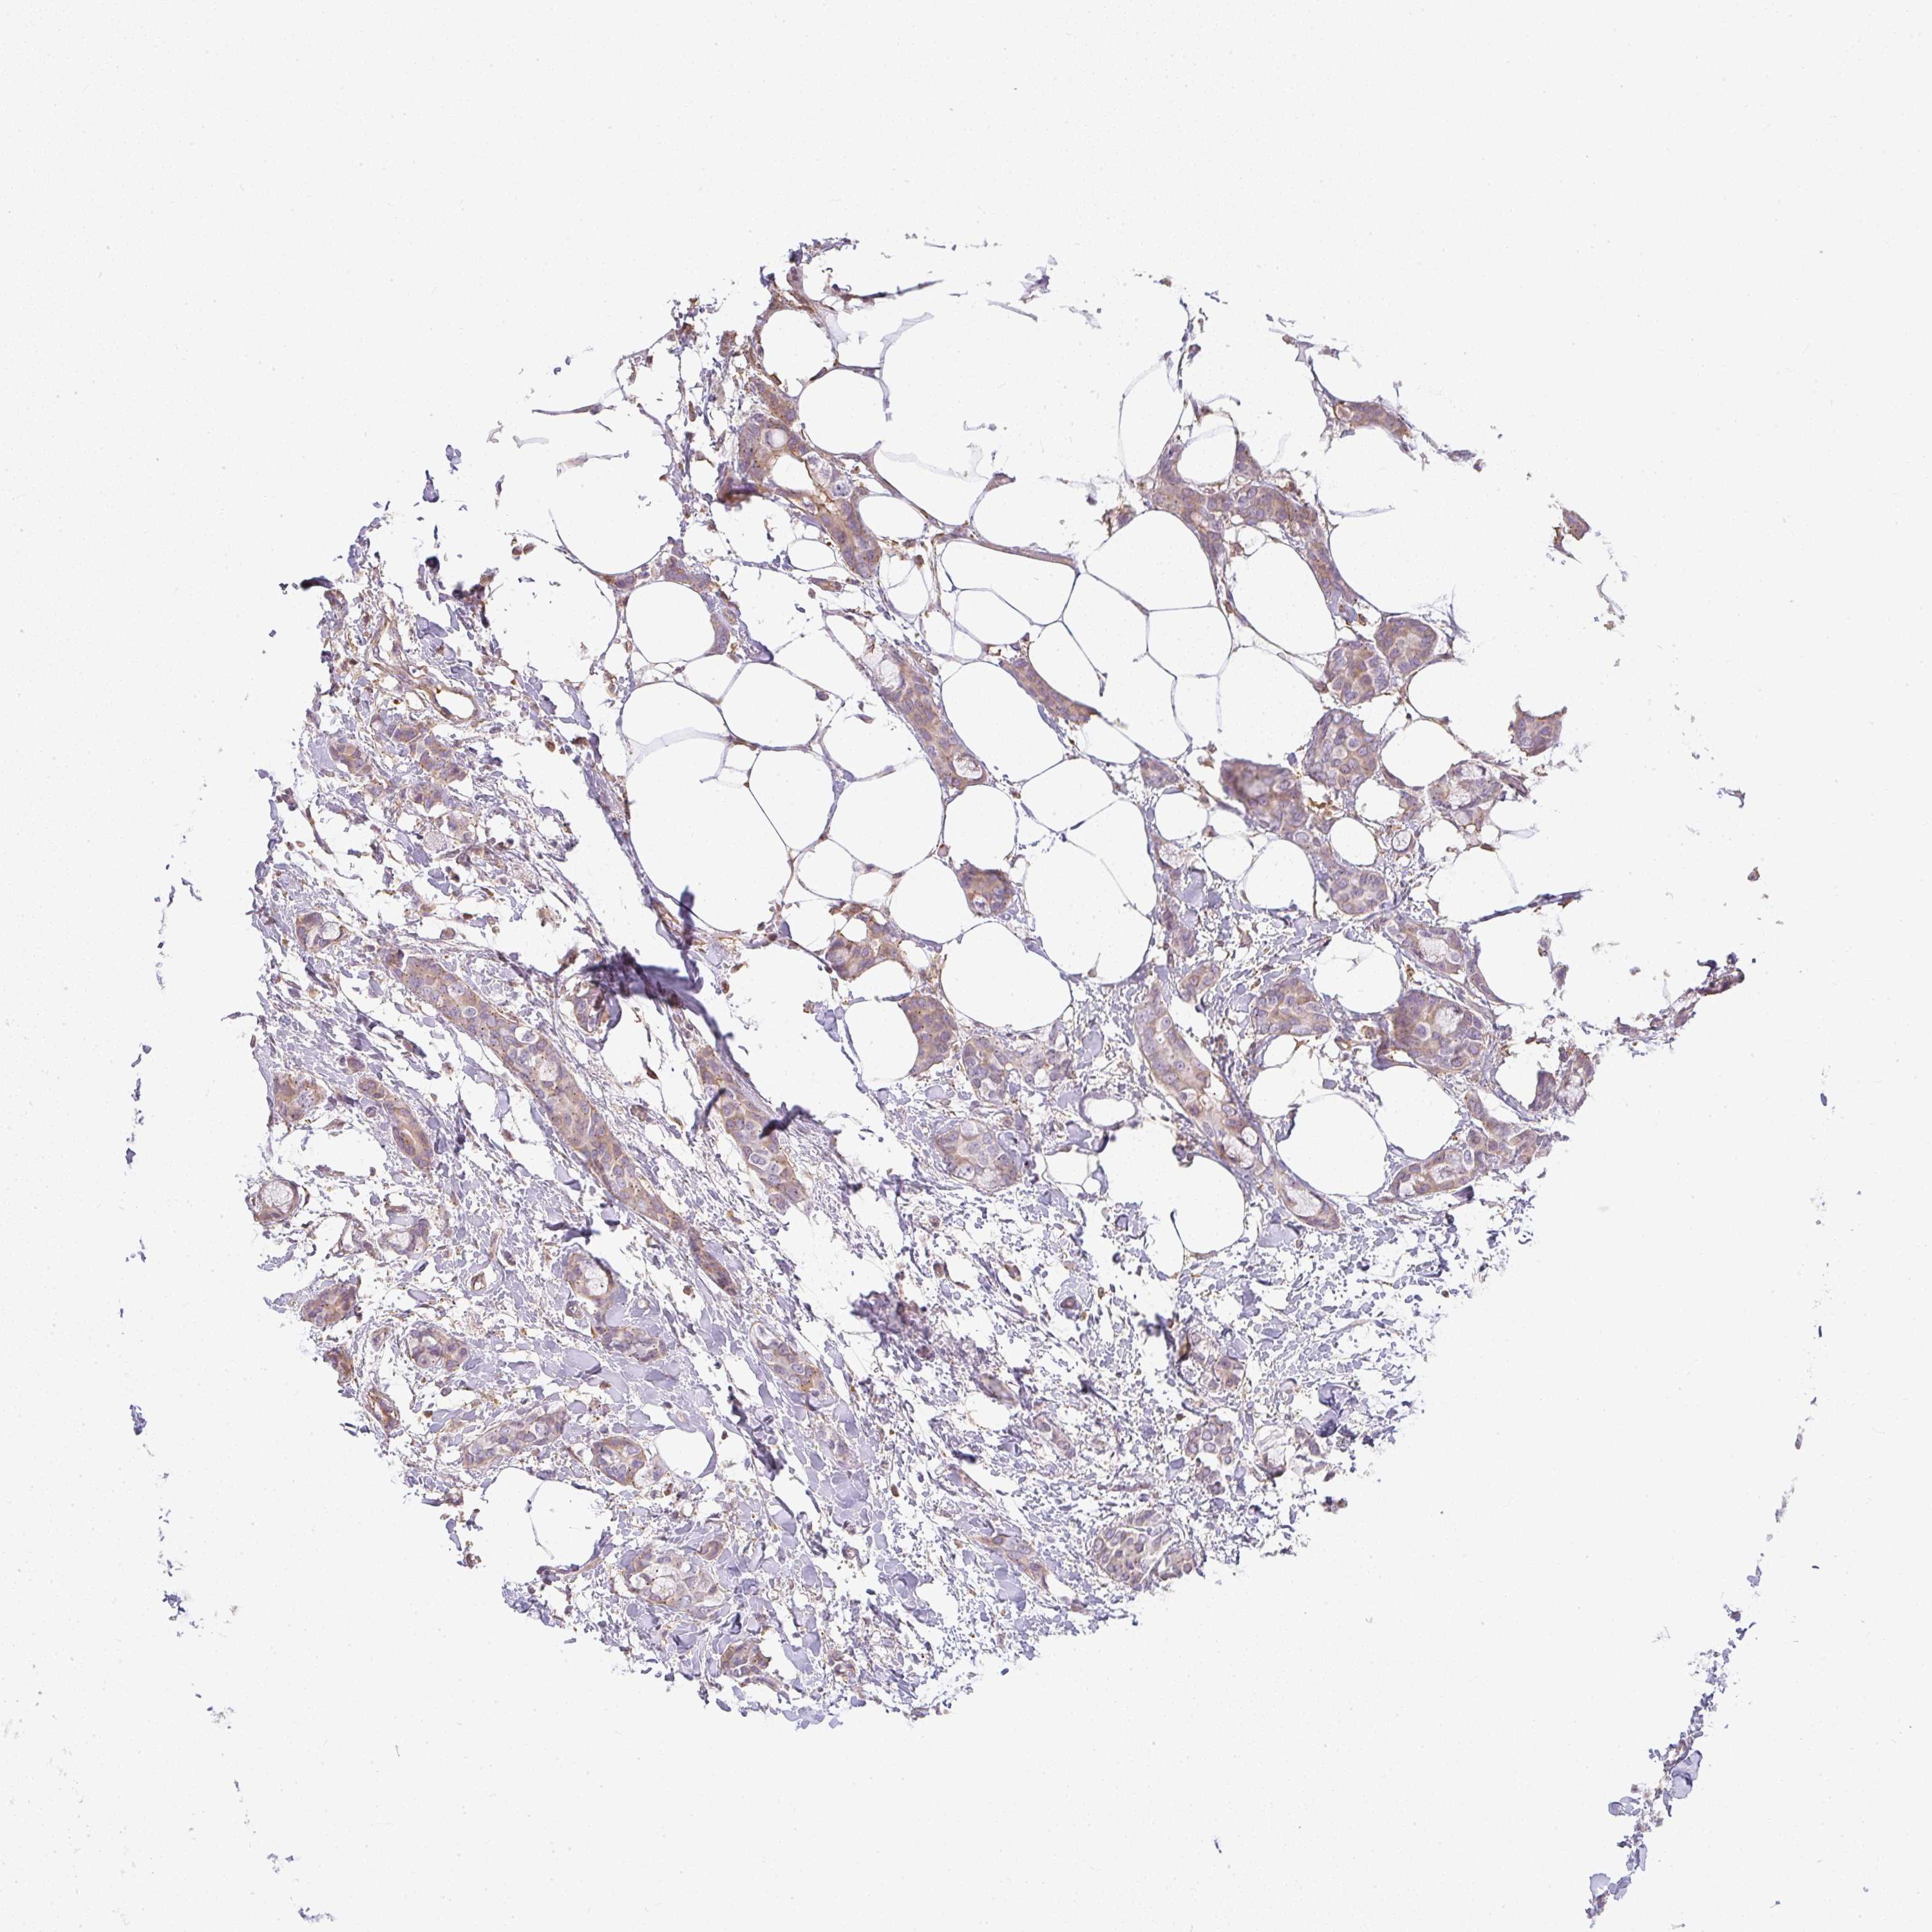

CANCER BREAST CANCER Show tissue menu

BRCA TCGA BRCA VALIDATION PROTEIN EXPRESSION

Breast cancer

Human cancer